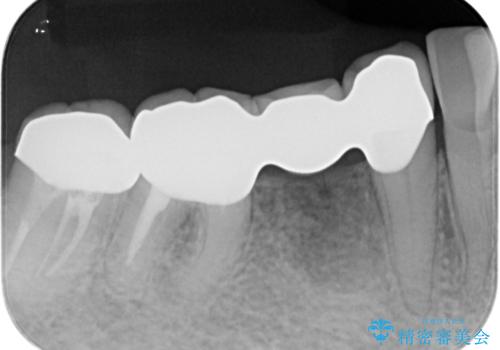

- 他院で右下小臼歯が保存不可能と言われ来院。当院の判断でも残念ながら抜歯となり、欠損部は抜歯後ブリッジにしました。右下奥2本が連結されていたため、そこは各々切り離した形で被せ物のやり替えも行っています。

- 約60万円 右下④5⑥:ジルコニアクラウンブリッジ 11万円×3 仮歯 1万円×3 根管治療費用別途費用は治療当時の料金となります

抜歯後3か月ほど仮歯で生活していただき、欠損部の歯肉の状態が安定してからブリッジを入れています。